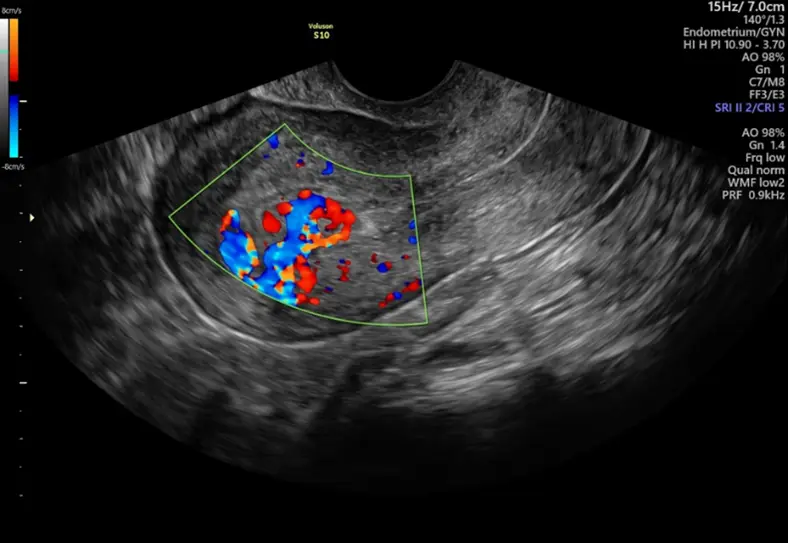

Heavy menstrual bleeding is often ignored as normal, but persistent heavy periods may indicate menorrhagia. This condition can lead to anemia, fatigue, and serious gynecological issues. A pelvic ultrasound helps identify causes like fibroids, thickened endometrium, hormonal imbalance, or early uterine disorders, enabling timely diagnosis and effective treatment.